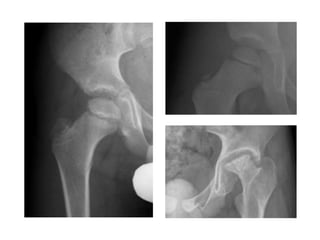

• Cadera 41% rodilla 23%

• Radiografías

• En cadera tomar ultrasonido.

Diagnóstico diferencial ... PERLAS dolor en

CADERA

• Diferenciar causas de dolor en

la cadera del paciente

pediatrico

• No retrasar Diagnósticos de

Urgencia

• Diferenciación clínica

Artritis Séptica

• Urgencia en Ortopedia

• Daño y destrucción de

cartílago articular irreversible

• lesión a la cadera en horas

(mayor a 8 hrs)

• inoculación hematogena o por

contigüidad

• Mas común en neonatos

>2años

• focos múltiples …

Legg Calve Perthes

• 1910.

• Etiología ? NAV

• Masculino 4>1 Femenino

• Bilateral 20% = 18 meses

• 3 - 10 años